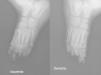

Niña de 3 años de edad, que presenta desde los pocos meses de vida distrofia ungueal bilateral en las uñas de los pies junto con lesiones intertriginosas interdigitales, sin afectación de las extremidades superiores ni de otros anejos cutáneos (fig. 1). Asocia fascies redondeada, mentón puntiagudo y retrognatia leve1 (fig. 2). Exploración física por aparatos, normal. Embarazo, parto y periodo neonatal sin enfermedad. EG de 40 semanas y somatometría al nacimiento adecuada, con un peso de 3.300 g (p50), talla de 49cm (p50) y perímetro cefálico de 33cm (p10-25). Crecimiento adecuado con el peso, la talla y el perímetro cefálico en torno al percentil 50 a los 3 años de edad. Desarrollo psicomotor, normal. Como antecedentes familiares destacan madre y abuela materna con distrofias ungueales en los pies, con uñas hipercurvadas. El cultivo de hongos de las lesiones intertriginosas fue negativo y la radiografía de ambos pies muestra ausencia de falanges distales del 3.er y 4.° dedos de ambos pies (fig. 3).

Radiografía simple oblicua de los pies izquierdo y derecho: ausencia de las falanges distales del 3.er y 4.° dedos del pie izquierdo, ausencia de las falanges distales del 3.er, 4.° y 5.° dedos del pie derecho, y reabsorción del extermo distal de la falange proximal del resto de los dedos de los pies en ambos pies.